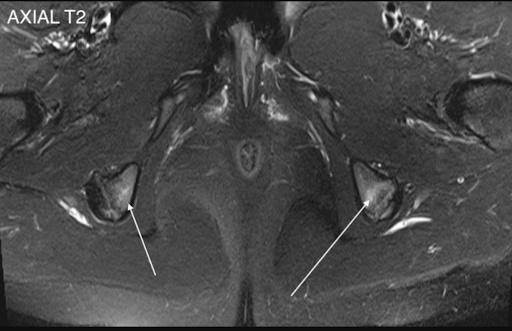

Mid teen footballer presenting with bilateral inferior gluteal, proximal hamstring and medial groin pain. This was accompanied with an increased training intensity with new step over and pivoting drills. MRI showed bilateral ischial apophysitis (bone marrow oedema arrowed in figure 6 and 7) and adductor origin inflammation (not shown).

Figure 6

Figure 7